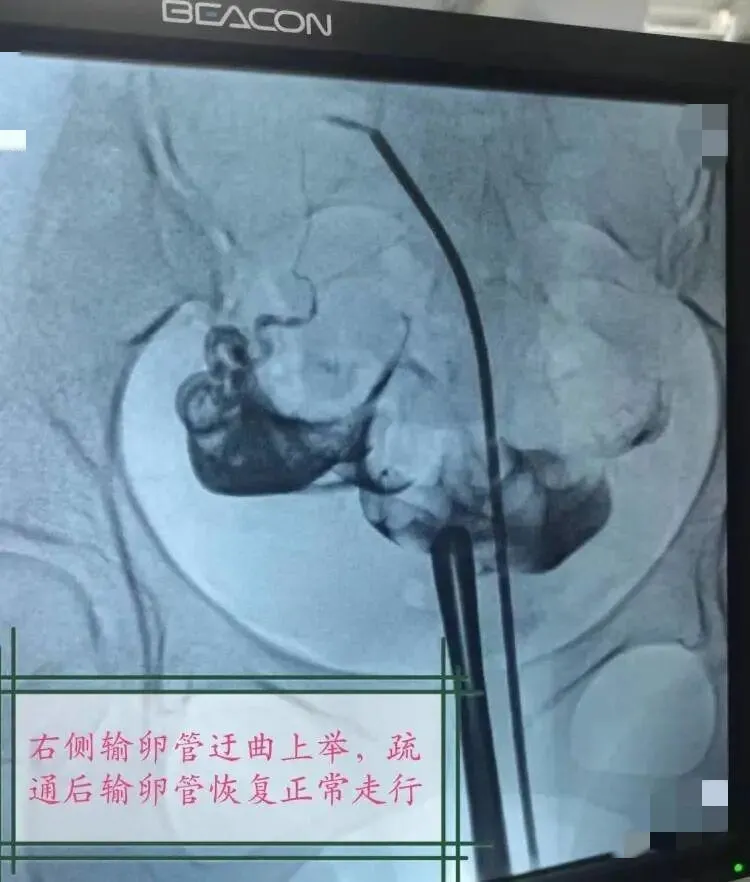

近日,我院收治了一位被不孕症困扰多年的患者,该女士5年来,因为不孕反复就诊多家医院和诊所,中药西药没少喝,却迟迟没有迎来“好孕”。1月前,她慕名来到我院的妇科门诊,在周愦珍主任的建议下,进行了输卵管造影术,结果显示左侧输卵管不通,右侧输卵管上举迂曲。患者得此消息,焦虑不已。周主任团队为其精心制定手术方案,进行了“输卵管导丝介入疏通术”,短短几分钟,为患者解决了困扰多年的问题,夫妻俩开心极了,直言“好孕”到了!

“输卵管导丝介入疏通术”是从美国引进的技术,主要用于治疗输卵管堵塞导致的不孕症。输卵管导丝介入疏通术,采用微创技术,可作为输卵管近段阻塞的首选再通方法,操作简单,不开刀、无痛苦,安全有效,不良反应轻,可达到诊断与治疗的双重目的,已在临床得到推广普及。该技术是集检测、扩容、通液三位一体的高精人工智能辅助生育技术。它通过dsa造影技术精确确定堵塞部位,利用在妇科腹腔镜、宫腔镜两大技术领域的探查与治疗优势,在电视监视和输卵管镜的直视下无创精确介入,将一根导管通过阴道放至子宫输卵管的开口部位,管中有根0.38毫米的铂金导丝,这根导丝比我们的头发丝还要细,经宫颈将导管导丝送入输卵管阻塞部位,然后在电视监视和输卵管镜的直视下,通过局部介入技术将输卵管疏通,并置入预防粘连的药物,对患者进行子宫输卵管疏通手术。